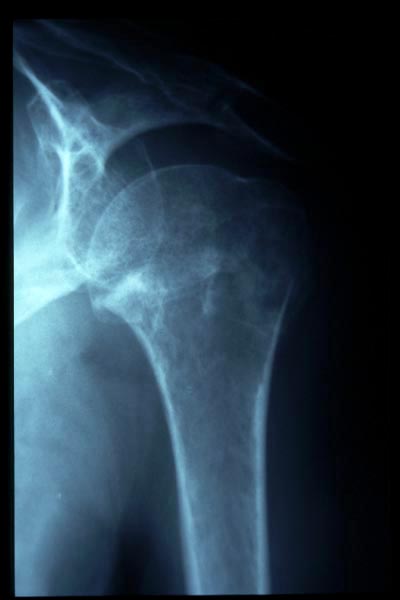

Fractura impactada de húmero .